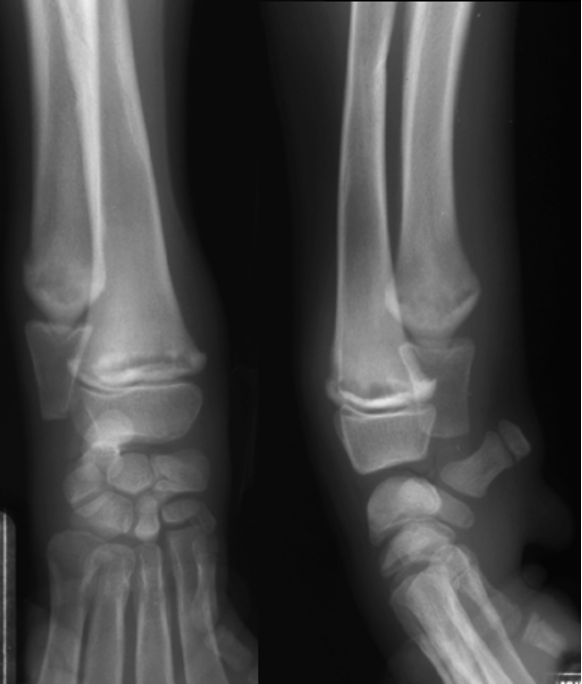

premature distal ulnar physis closure roentgen signs

gap - ulna and humerus, and gap at the bottom of ulna and carpus

cranial bowing of radius

premature distal radius physis closure roentgen signs

gap - radius and humerus, radius and carpus

no real ALD

which physis closed early

ulna

radius